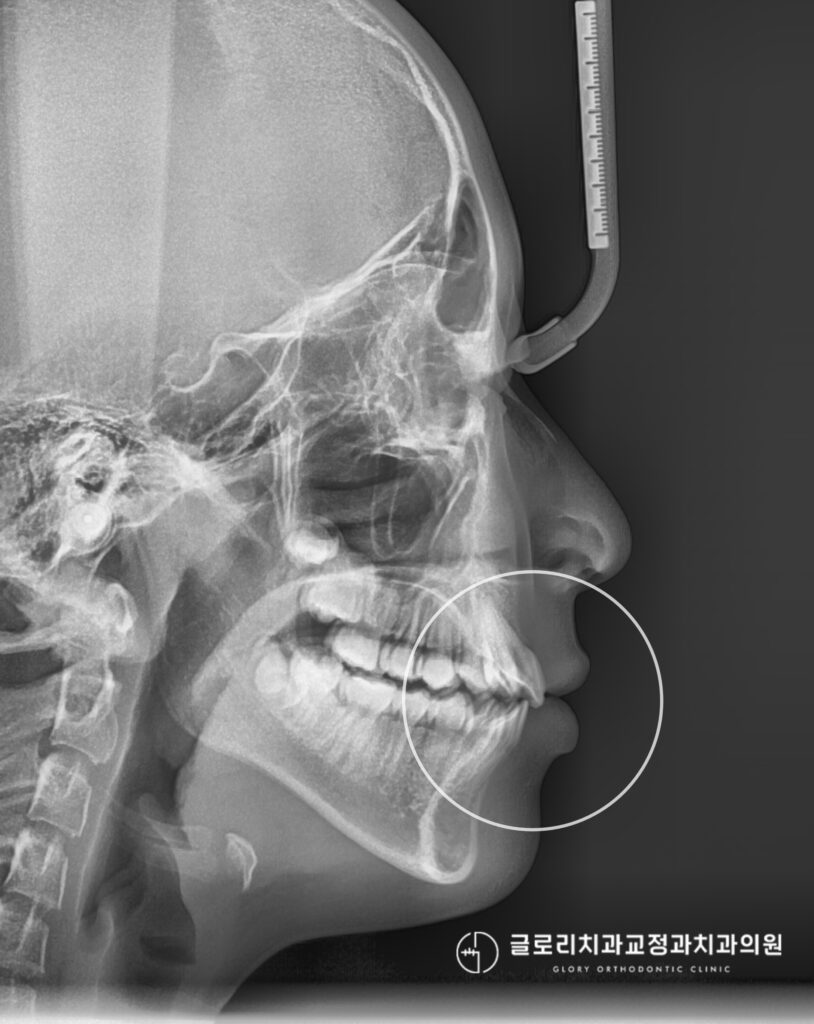

상봉동 치과 에서 보여드리는 최종 구외사진을 통해 측면에서 바라보았을 때

돌출감과 안모가 자연스럽게 개선되었으며 입술이 무리 없이 자연스럽게 다물어지는 조화로운 측모를 보여줍니다.